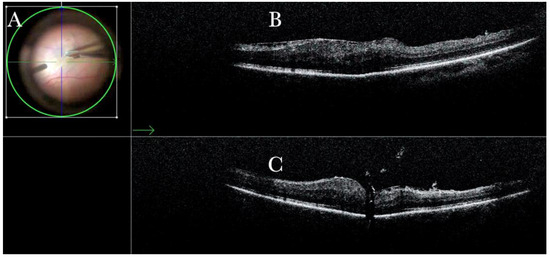

Figure 12.

(A) Microscope view of the macular area in case of myopic traction maculopathy in stage 4C (macular detachment with full-thickness macular hole (FTMH)) after implanting a macular buckle and peeling the inner limiting membrane (ILM) creating an ILM flap. The transillumination of a fiber optic inserted into the buckle allows us to guess the location of the buckle itself. The FTMH is not visible under the air. (The green box indicates the field-of-view of the OCT scan, the green and blue lines within the green box show the vertical and horizontal scan planes). (B) The intraoperative optical coherence tomography (i-OCT) B horizontal (green arrow) scan shows, very clearly, the indentation of the macula from the scleral side due to the presence of a macular buckle. (C) The i-OCT B vertical scan shows, very clearly, the indentation of the macula. The white arrow shows the FTMH, which is now well-positioned over the buckle, and the presence of the ILM flap even under the air.